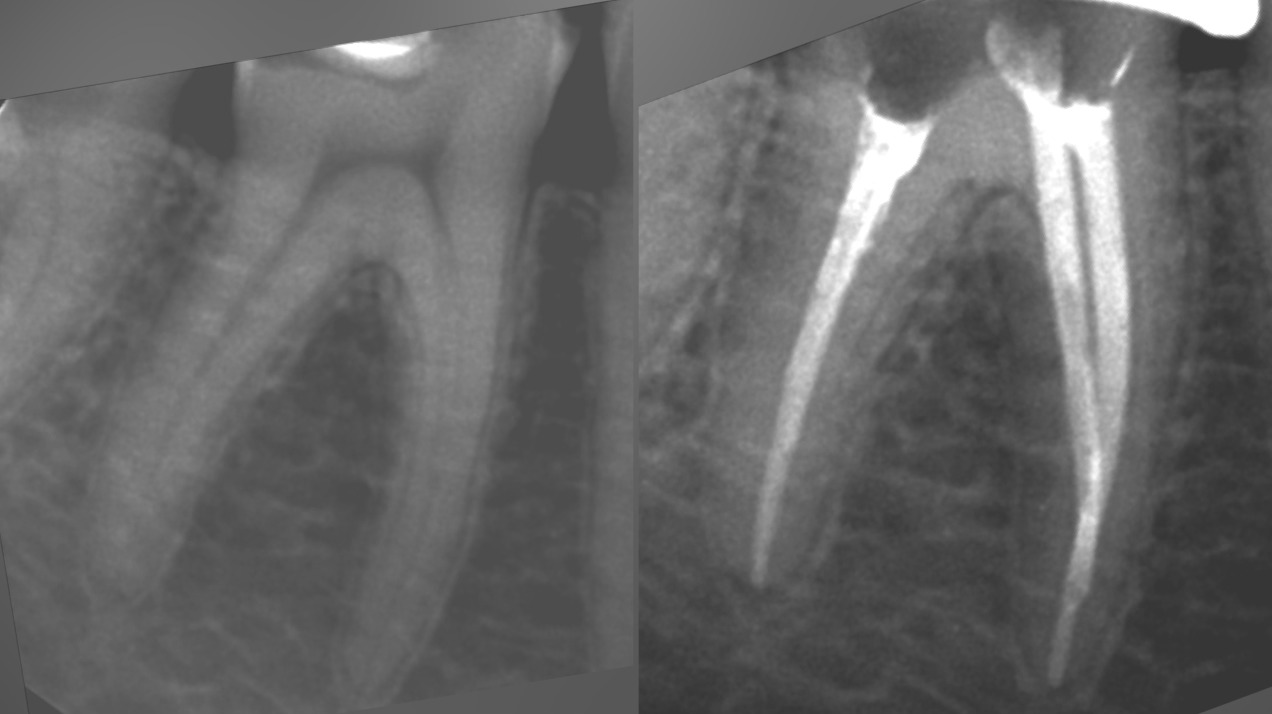

• Диагностика и лечение кариеса и его осложнений (пульпиты, периодонтиты)

• Эндодонтическое лечение корневых каналов с использованием стоматологического микроскопа